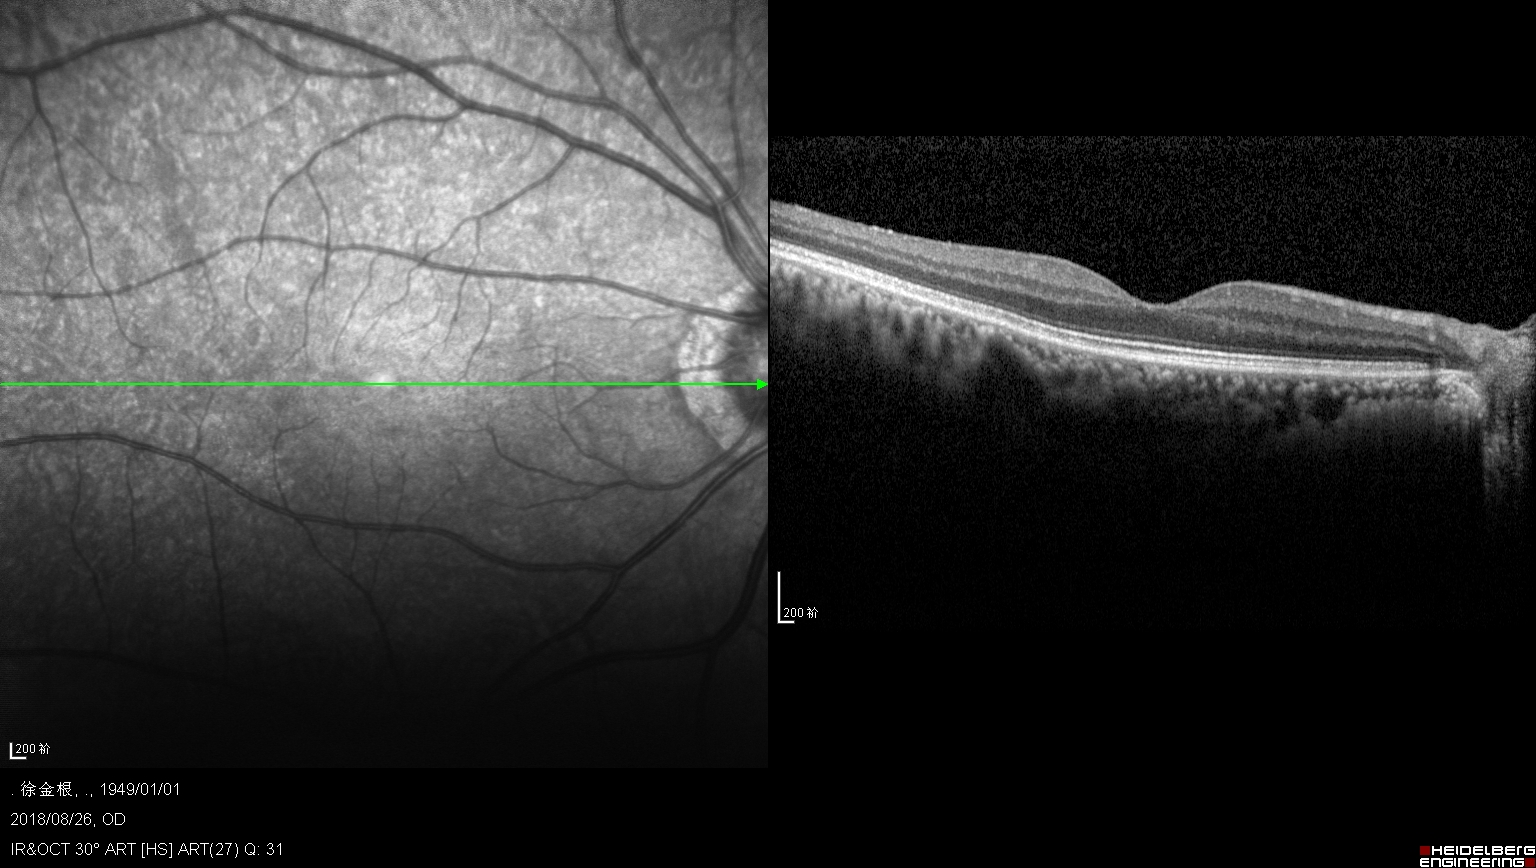

正常黄斑形态

左眼黄斑被玻璃牵引黄斑即将形成裂孔

右眼黄斑裂孔,上方可以看见被牵拉掉的组织